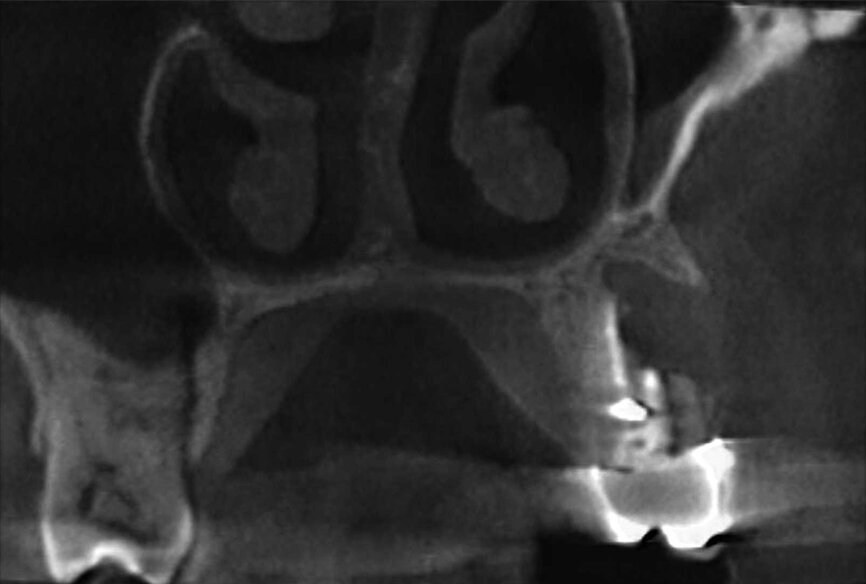

Le cas avec lequel je souhaite commencer mon exposé clinique est un exemple parfait de la difficulté à définir l’origine des symptômes d’un patient, par l’examen d’une simple radiographie intraorale. Non seulement l’examen 2D ne permet pas d’établir avec certitude la présence d’une lésion, mais surtout, il est impossible d’en déterminer la taille, la morphologie et le type. Au contraire, une analyse de l’imagerie 3D offre une image claire de la situation clinique. Chez ce patient, les coupes coronales et sagittales révèlent la présence d’une importante lésion s’étendant de l’apex de la racine mésiale de cette molaire jusqu’à la zone de furcation, tandis que les coupes axiales nous permettent d’analyser précisément l’anatomie endodontique et, en particulier, la forme de la racine mésiale, qui apparaît fusionnée avec la racine palatine. Un panorama complet du cas peut donc guider le processus de décision et orienter le plan de traitement vers une modalité bien précise de traitement (Figs. 1–4).